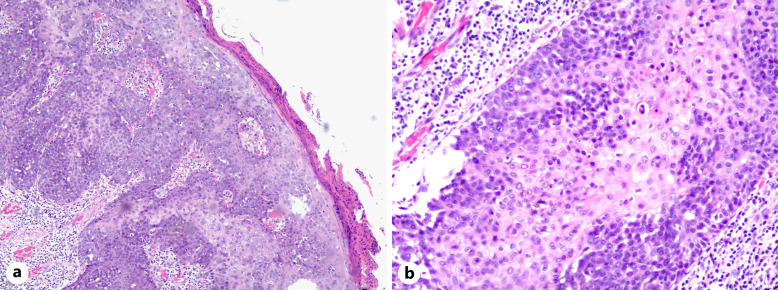

Case presentation: A 64-year-old female presented with a right lumbar mass persisting for over 2 decades, exhibiting progressive enlargement in the past 5 years. Clinical examination revealed a solitary reddish-brown proliferative plaque (3.5 cm × 4.0 cm) on the right waist, characterized by irregular borders, a rough surface, and reddish-brown crusts. Histopathological findings included hyperkeratosis, irregular epidermal hyperplasia, hypertrophic stratum spinosum, and tumor cells displaying pale eosinophilic cytoplasm, vacuolated nuclei, small nucleoli, and atypical mitotic figures. Notably, tumor cells were confined to the epidermis without dermal invasion. The patient underwent local extended excision, and postoperative surveillance over 15 months demonstrated no evidence of recurrence or lymph node metastasis.